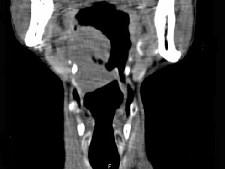

问题 男,74岁,咽喉部不适一年余,近两三个月咽喉疼痛,吞咽困难,CT如图所示,最可能诊断是()

选项 A.喉癌 B.会厌癌 C.声带癌 D.声门下区癌 E.跨声门型癌

答案 B